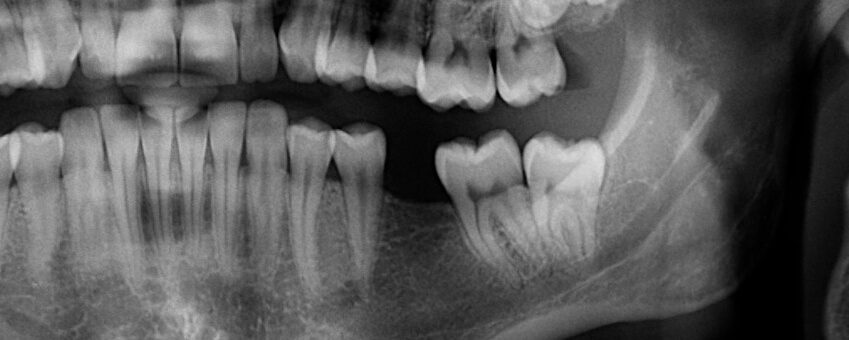

A tooth may require extraction for a variety of reasons. If the tooth is impacted in the gumline (particularly common with wisdom teeth), if there are serious crowding issues, or if the tooth is too damaged, rotted, or loose to be saved with root canal treatment, Dr. Cromwell may determine that extraction is the best option. After the recovery period is over, it will be time to begin taking the prosthodontic or orthodontic steps needed to fill in your smile.